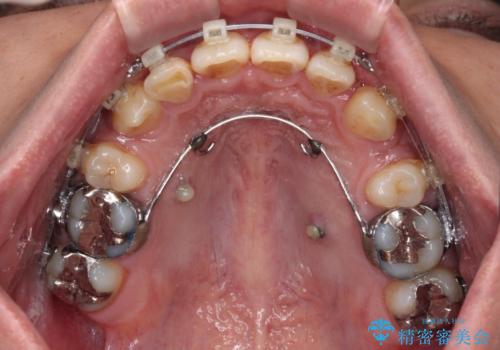

- クリアブラケット

補助装置を併用することで効率的に八重歯や正中位置の改善を達成することができました。